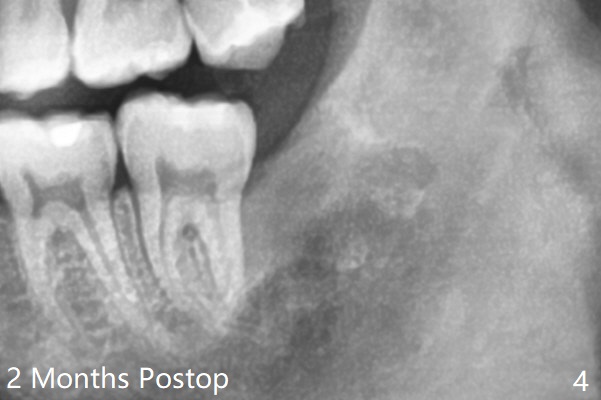

A 21-year-old man returns to clinic with pain and swelling at #17 (Fig.1,2). After multiple sectioning, the tooth is extracted with insertion of collagen plug post extraction in the late afternoon. The patient complains of sharp pain during local anesthetic injection. Postop paresthesia is gradually getting better, but gets worse 2 months postop (Fig.3,4). Neurotin is prescribed. Vitamin B1 and B12 are recommended. OMFS is suggested. 21岁男因左下智齿肿痛要求拔除(图一,二),术中发现轻度颊侧阻生,使用一只利多卡因,一只Septocaine,一般前者block anesthesia,后者infiltration。多次用手机切割牙齿,拔除后牙槽窝放置一个胶原塞(减少术后干槽症),4-0铬羊肠线缝合。术后两个月病人突然回来,主诉局麻注射造成剧痛,术后下嘴唇麻木开始逐渐好转,最近麻木突然加重(图三,四)。左下智齿牙槽窝已经愈合。处方:Neurotin;推荐维生素B1, B12;建议口外会诊。还能做什么?